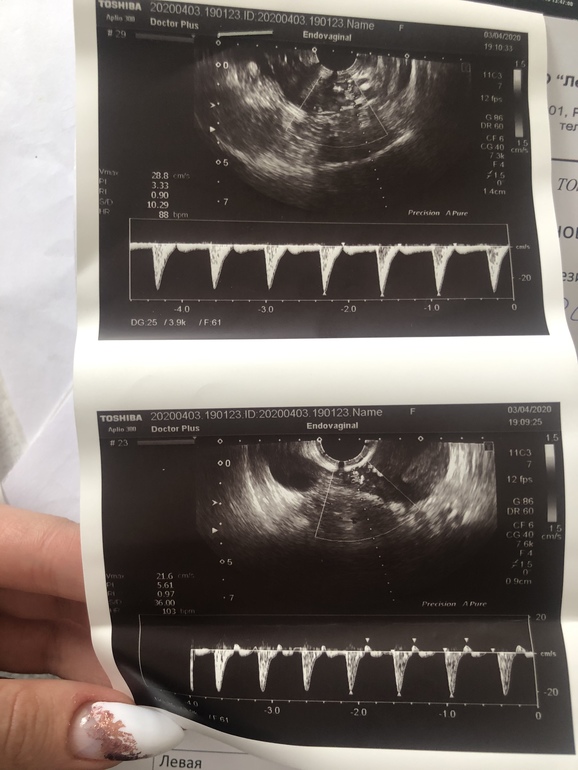

Замершая беременностьтвуйте. Подскажите, пожалуйста. Было 2 беременности подтверждённые лишь по тестам и хгч. Так как не узи не успевала сходить, начинались месячные. Чистки не было. Все выходило само. Месячные начинались на 10-11 день задержки в обоих случаях. Ставят диагноз - привычное невынашивание. Сейчас назначили - дивигель, утрожестан, курантил и акиовегин. Результаты узи и анализов прикрепляю. Подскажите, возможно ли беременность нормальная при таких показателях? Фото узи и гормонов прикрепляю

Выкедыши у вас скорее по тому что не хватает гормонов, для этого вам их назначили дивигель + утражестан. Плохой кровоток понятие относительное,вы могли перед узи просто посидеть в очереди от этого и кровоток плохой на узи. Но, тем временем вам назначили курантил+Актовегин эти препараты очень хорошо выравнивают кровоток. Только лучше Актовегин проколоть 10 уколов, а потом пить его в таблетках. Таблетки имеют долгий и накопительный эффект. А уколы действуют сразу.

Нарушение кровотока это конечно не очень хорошо . Плюс пусть ваш муж сдаст спермограмму

Сказали ,что из за тонкого эндометрия ( тогда он был 5,6) и плохого кровотока